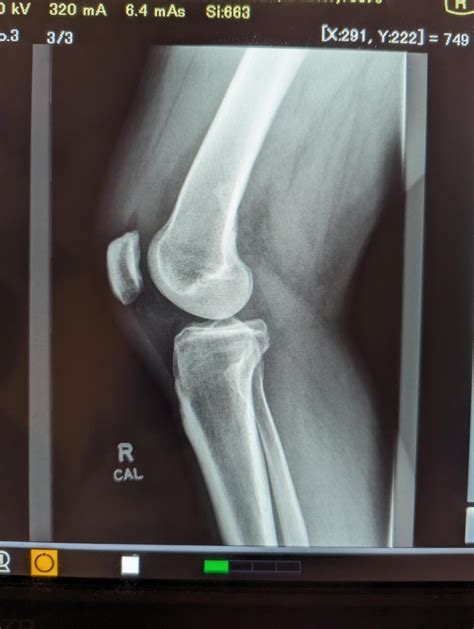

Lateral Knee Xray

Understanding the importance of a Lateral Knee Xray is crucial for anyone dealing with knee injuries or conditions. This diagnostic tool provides valuable insights into the structure and health of the knee joint, helping healthcare professionals make informed decisions about treatment and management. In this post, we will delve into the details of a Lateral Knee Xray, its significance, the procedure involved, and how to interpret the results.

What is a Lateral Knee Xray?

A Lateral Knee Xray is a type of radiographic imaging that captures a side view of the knee joint. This view is essential for evaluating the alignment of the bones, the condition of the joint spaces, and the presence of any abnormalities such as fractures, dislocations, or arthritis. The lateral view complements other views, such as the anteroposterior (AP) and oblique views, to provide a comprehensive assessment of the knee.